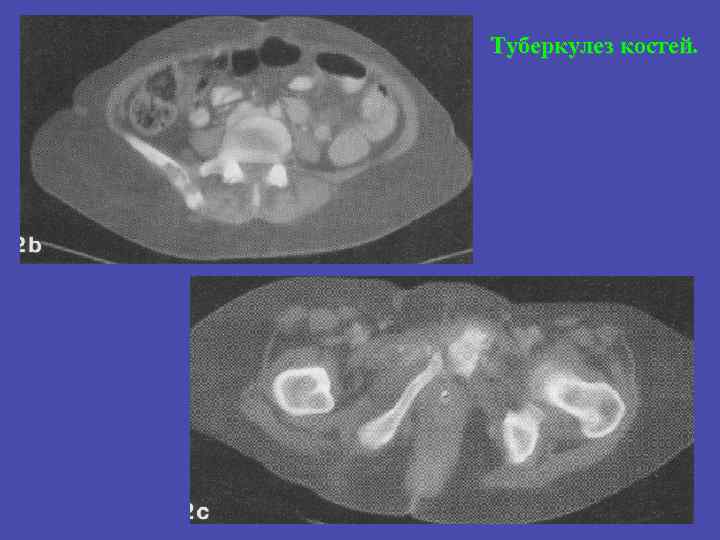

Туберкулез костей.